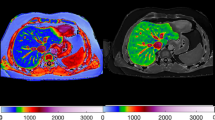

For the enhanced scanning procedure, 256-detector rows CT machine was used. From the diaphragmatic crest to the pubic symphysis, a 5 mm thick scan was performed along with a 0.75 mm thick thin layer reconstruction. A contrast medium was administered through a high-pressure syringe inserted into the anterior cubital vein. A dosage of 60–80 mL of the contrast medium containing 300 mg/mL of iodine was injected at a rate of 3.0–3.5 ml/s. After contrast injection, an arterial phase scan (25–35 s after) and an intravenous phase scan (65–90 s after) were performed.

Image segmentation and feature extraction

An original DICOM image was analyzed for radiomics features based on a two-dimensional region of interest (ROI), which was meticulously delineated by an experienced abdominal radiologist using manual segmentation on the axial slices of the MSCT images. The radiologist conducted this process while blinded to the clinical and pathological data. Care was taken to include the entire thickness of the bowel wall in the ROI, while excluding adjacent fat and vascular structures. This delineation was performed using ITK-SNAP software (www.itksnap.org), ensuring precision and consistency across all cases.

For the image resampling process, we employed the B-spline interpolation method, setting the target resolution to 1mm x 1mm x 1mm. The order of interpolation was set at 3, providing a balance between smoothness and accuracy in the resampling results. Various image preprocessing methods were applied, such as gray level co-occurrence matrix (GLCM), gray level run length matrix (GLRLM), gray level size zone matrix (GLSZM), and gray level dependence matrix (GLDM). To be specific, we quantized the image grayscale values into 64 discrete levels. For the application of various image preprocessing methods, a window size of 5mm x 5mm was utilized. Specifically, for the extraction of Gray Level Co-occurrence Matrix (GLCM) features, a pixel pair distance of 1 was set, and features were calculated in all four principal directions (0°, 45°, 90°, and 135°). At last, a total of 1,450 standardized radiomic features were extracted.